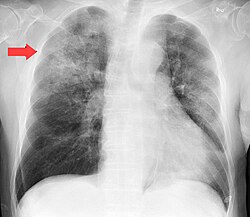

Zotiljam yoki pnevmoniya — oʻpka yalligʻlanishi, oʻpkaning infeksion kasalligi, mustaqil kasallik yoki boshqa kasalliklarning asorati hisoblanadi. Pnevmoniyani turli bakteriyalar (pnevmokokk, streptokokk, stafilokokklar) va viruslar qoʻzgʻatadi. Kasallikning yuzaga kelishi va rivojlanishiga odamning qattiq sovuq qotishi, jismoniy va ruhiy oʻta toliqishi, organizmning ichki zaharlanishi — intoksikatsiya hamda organizmning kasallikka qarshi kurashish qobiliyatini susaytiruvchi boshqa omillar sabab boʻladi, natijada yuqori nafas yoʻllariga mikroblar oʻtkir va surunkali, joyiga qarab chegaralangan sohalardagi yoki pnevmoniya (oʻpkaning butun bir boʻlagi zararlanadi) va oʻchoqli bronxopnevmoniya farq qilinadi.